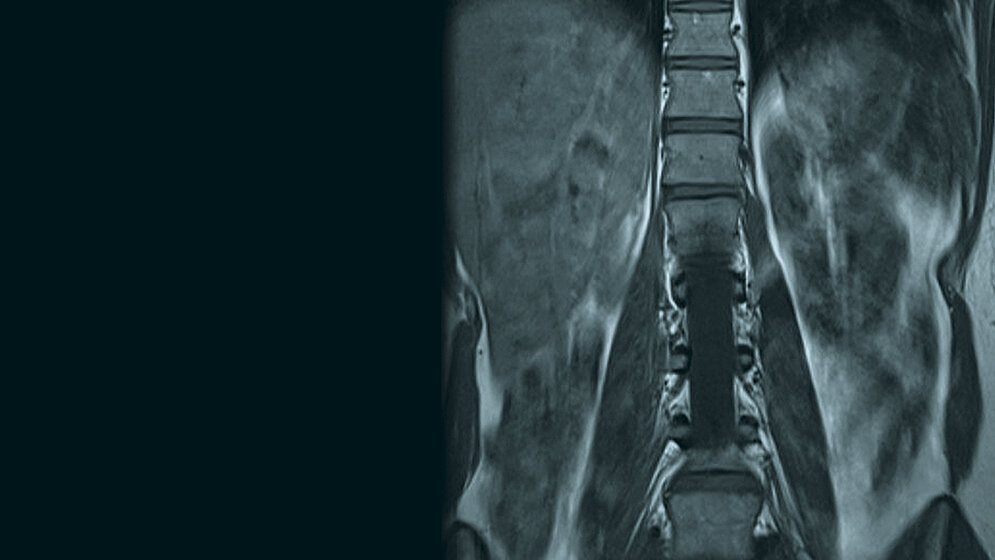

Die Nierenagenesie kann die einzige Malformation des Harntraktes sein oder auch mit anderen Erkrankungen des Urogenitalsystems vergesellschaftet sein. Auch Fehlbildungen der Nieren werden gelegentlich mit kardialen, spinalen und pulmonalen Malformationen zusammen beobachtet. Die MRT ist hilfreich bei der Differenzialdiagnostik, die in der CT oder im Ultraschall mehrdeutig ist.

Renal agenesis may be the only malformation in urinary system or associated with other diseases in urinary tract. Associated malformations of the kidney, heart, spinal cord and lung are frequently observed. MRI is particularly helpful for further differentiation of lesions that are equivocal on CT or ultrasound.